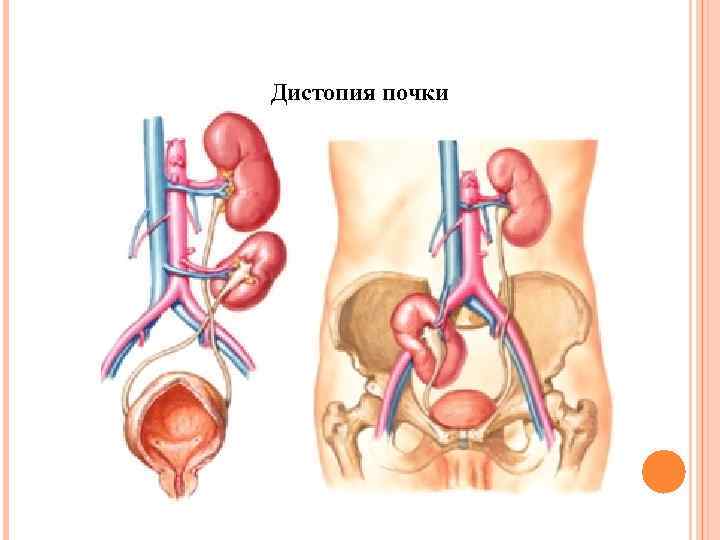

Дистопия почки

Дистопия почки